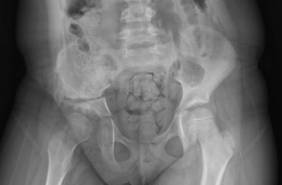

La displasia de cadera es una afección frecuente -afecta entre 1 de cada 100 a 1 de cada 1000 niños- que, diagnosticada a tiempo, puede corregirse con tratamientos ortopédicos sencillos y evitar secuelas graves a largo plazo. Recientemente, el doctor Díaz y equipo de Traumatología de Quirónsalud Málaga ha operado a una niña de seis años con síntomas y limitaciones en la vida diaria, como cojera y dolor con la deambulación, así como cambios a nivel de la cadera que ya no se podían corregir con tratamiento conservador", comparte el traumatólogo.

Tras ser valorada por el Dr. Díaz y ante los cambios estructurales irreversibles en la articulación de la paciente, determinó la necesidad de una intervención quirúrgica. "Este caso nos recuerda que un diagnóstico y tratamiento correctos y tempranos son esenciales para permitir un desarrollo normal de la cadera y prevenir complicaciones futuras".

La displasia de cadera puede deberse a factores familiares, gestacionales y ambientales y es más común en niñas y en bebés nacidos en presentación podálica. El diagnóstico precoz, mediante exploración física y ecografía en el nacimiento, permite iniciar tratamientos eficaces, como el arnés de Pavlik, que corrige la posición del fémur y favorece el desarrollo normal de la articulación.

"Cuanto más tarde se detecta la displasia, más complejos y menos efectivos resultan los tratamientos, pudiendo requerirse cirugías correctivas y generando consecuencias permanentes, como cojera, dolor crónico o limitación funcional", alarma.